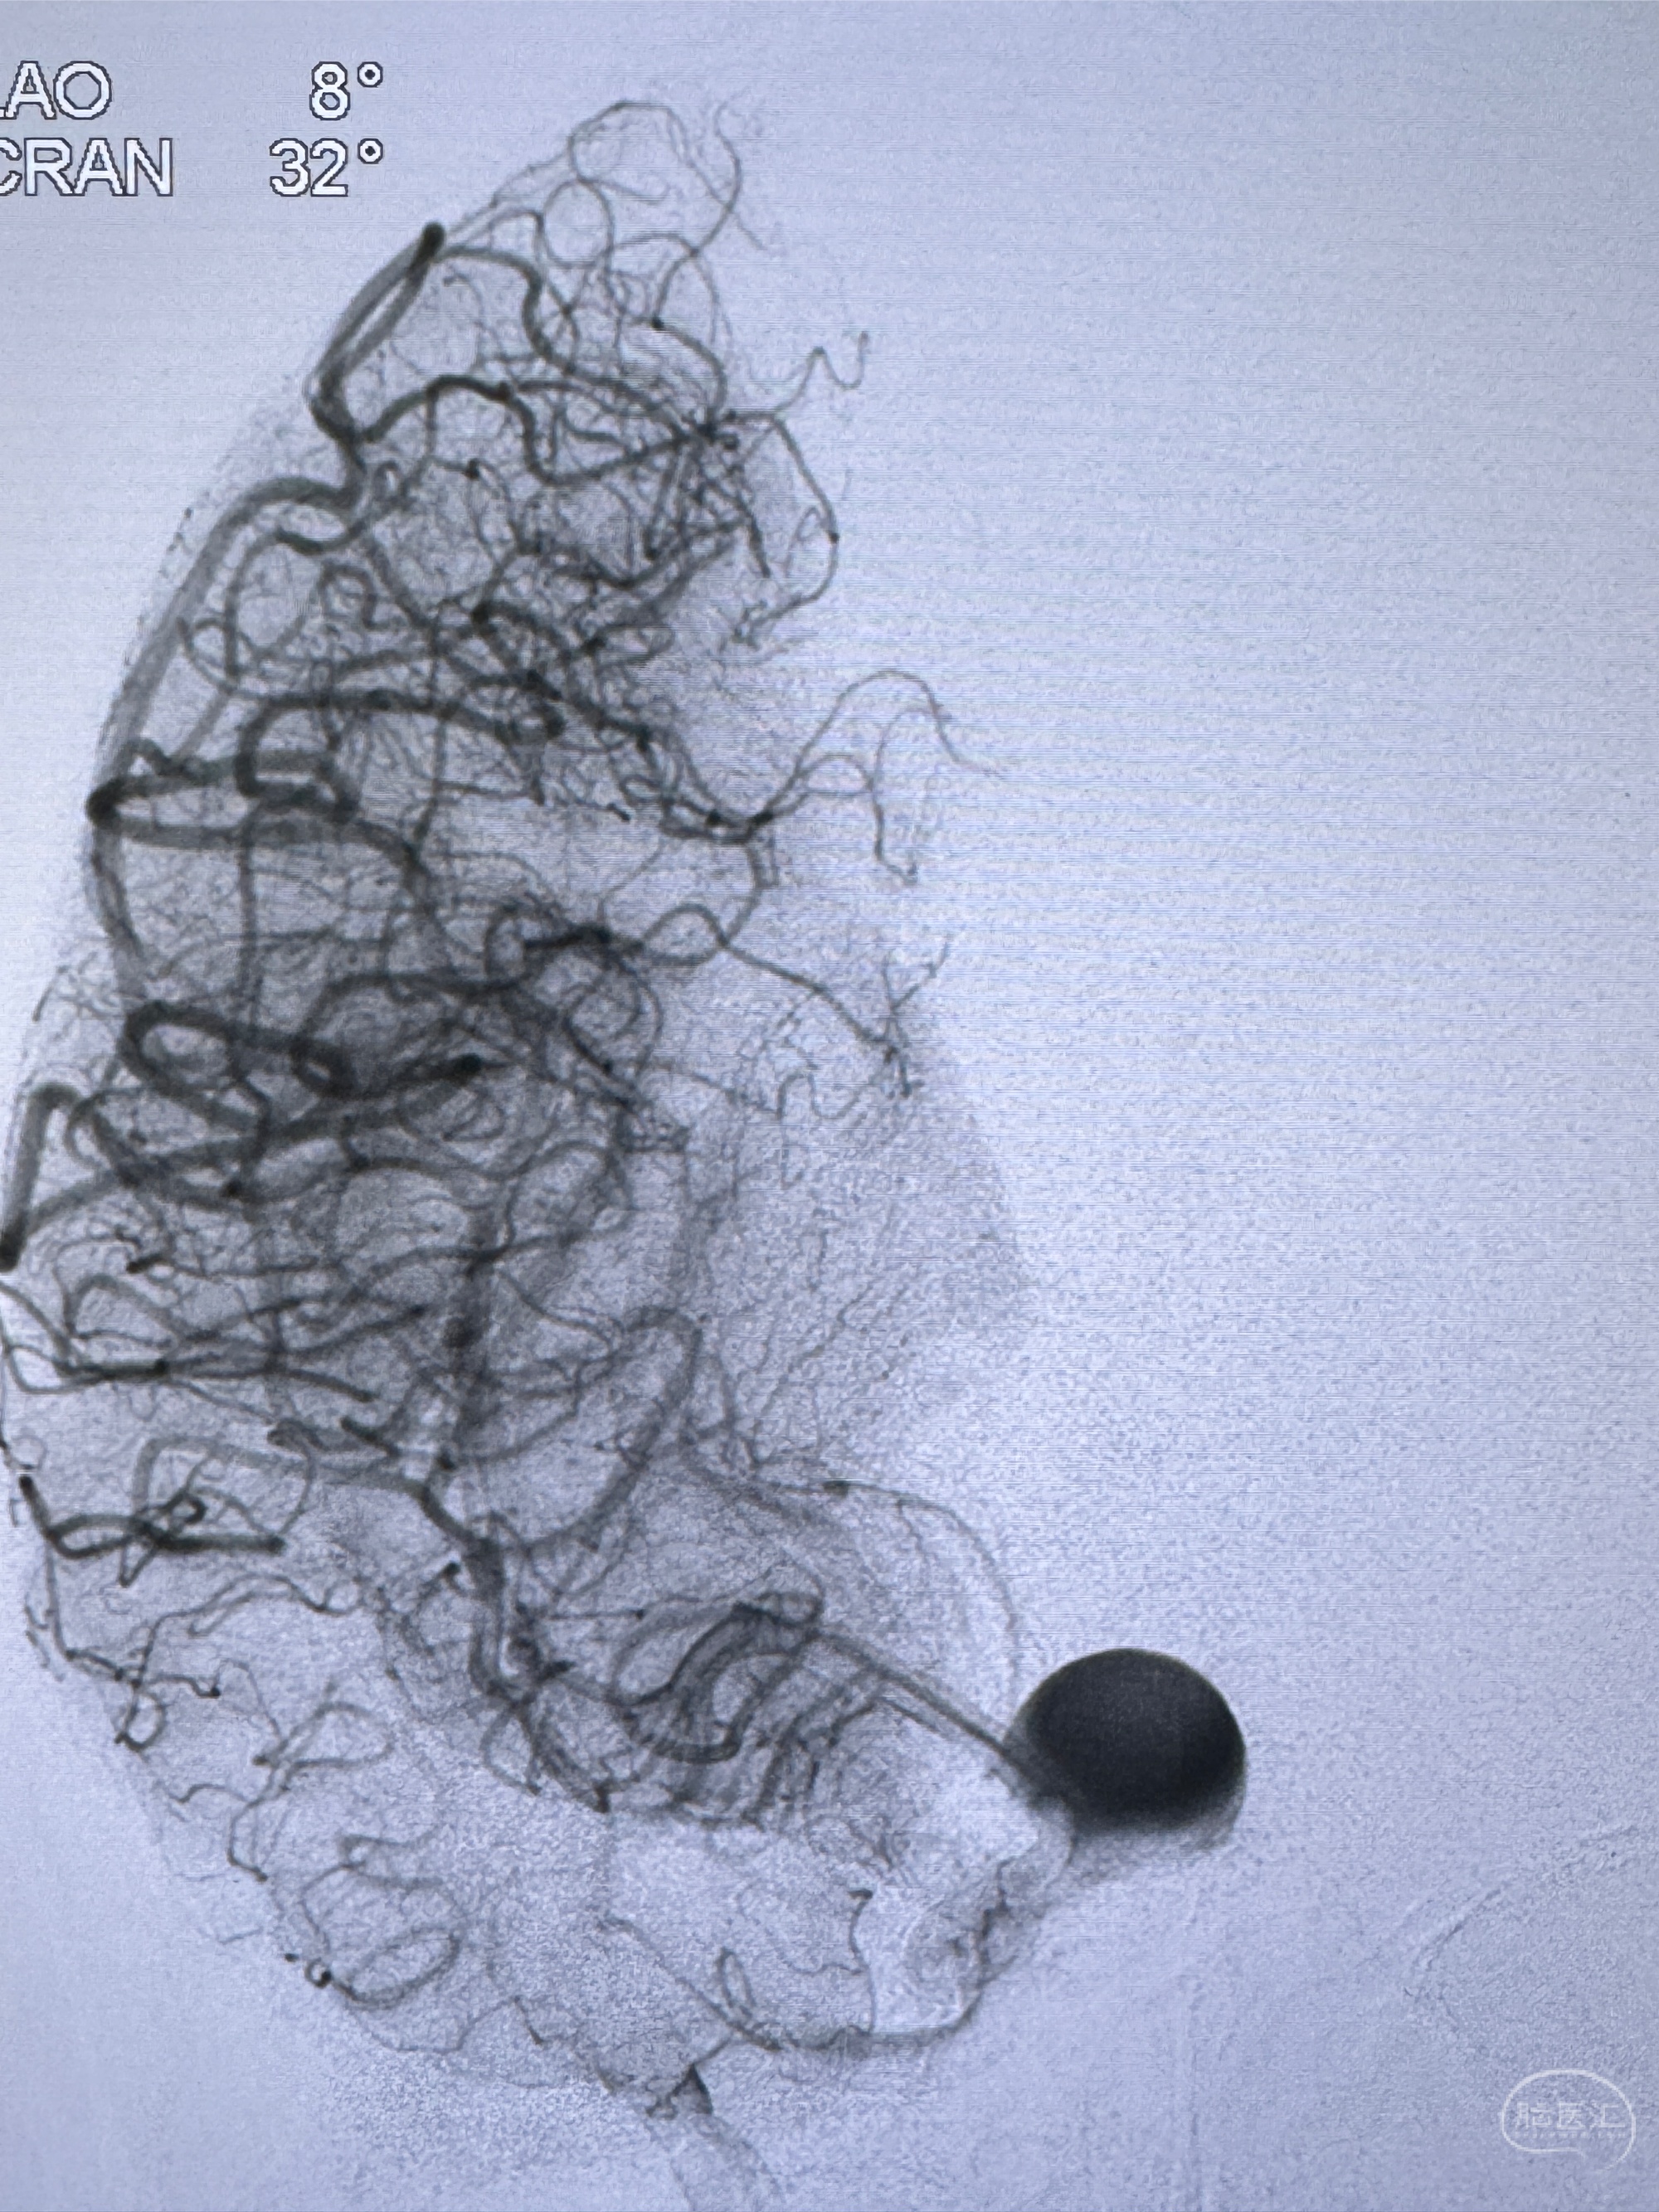

2023-12-08外院DSA:右侧颈眼动脉瘤,约13*12mm大小,压颈试验显示左右向及后向前代偿可

2023-12-18全麻下行DSA➕密网支架植入备弹簧圈辅助栓塞